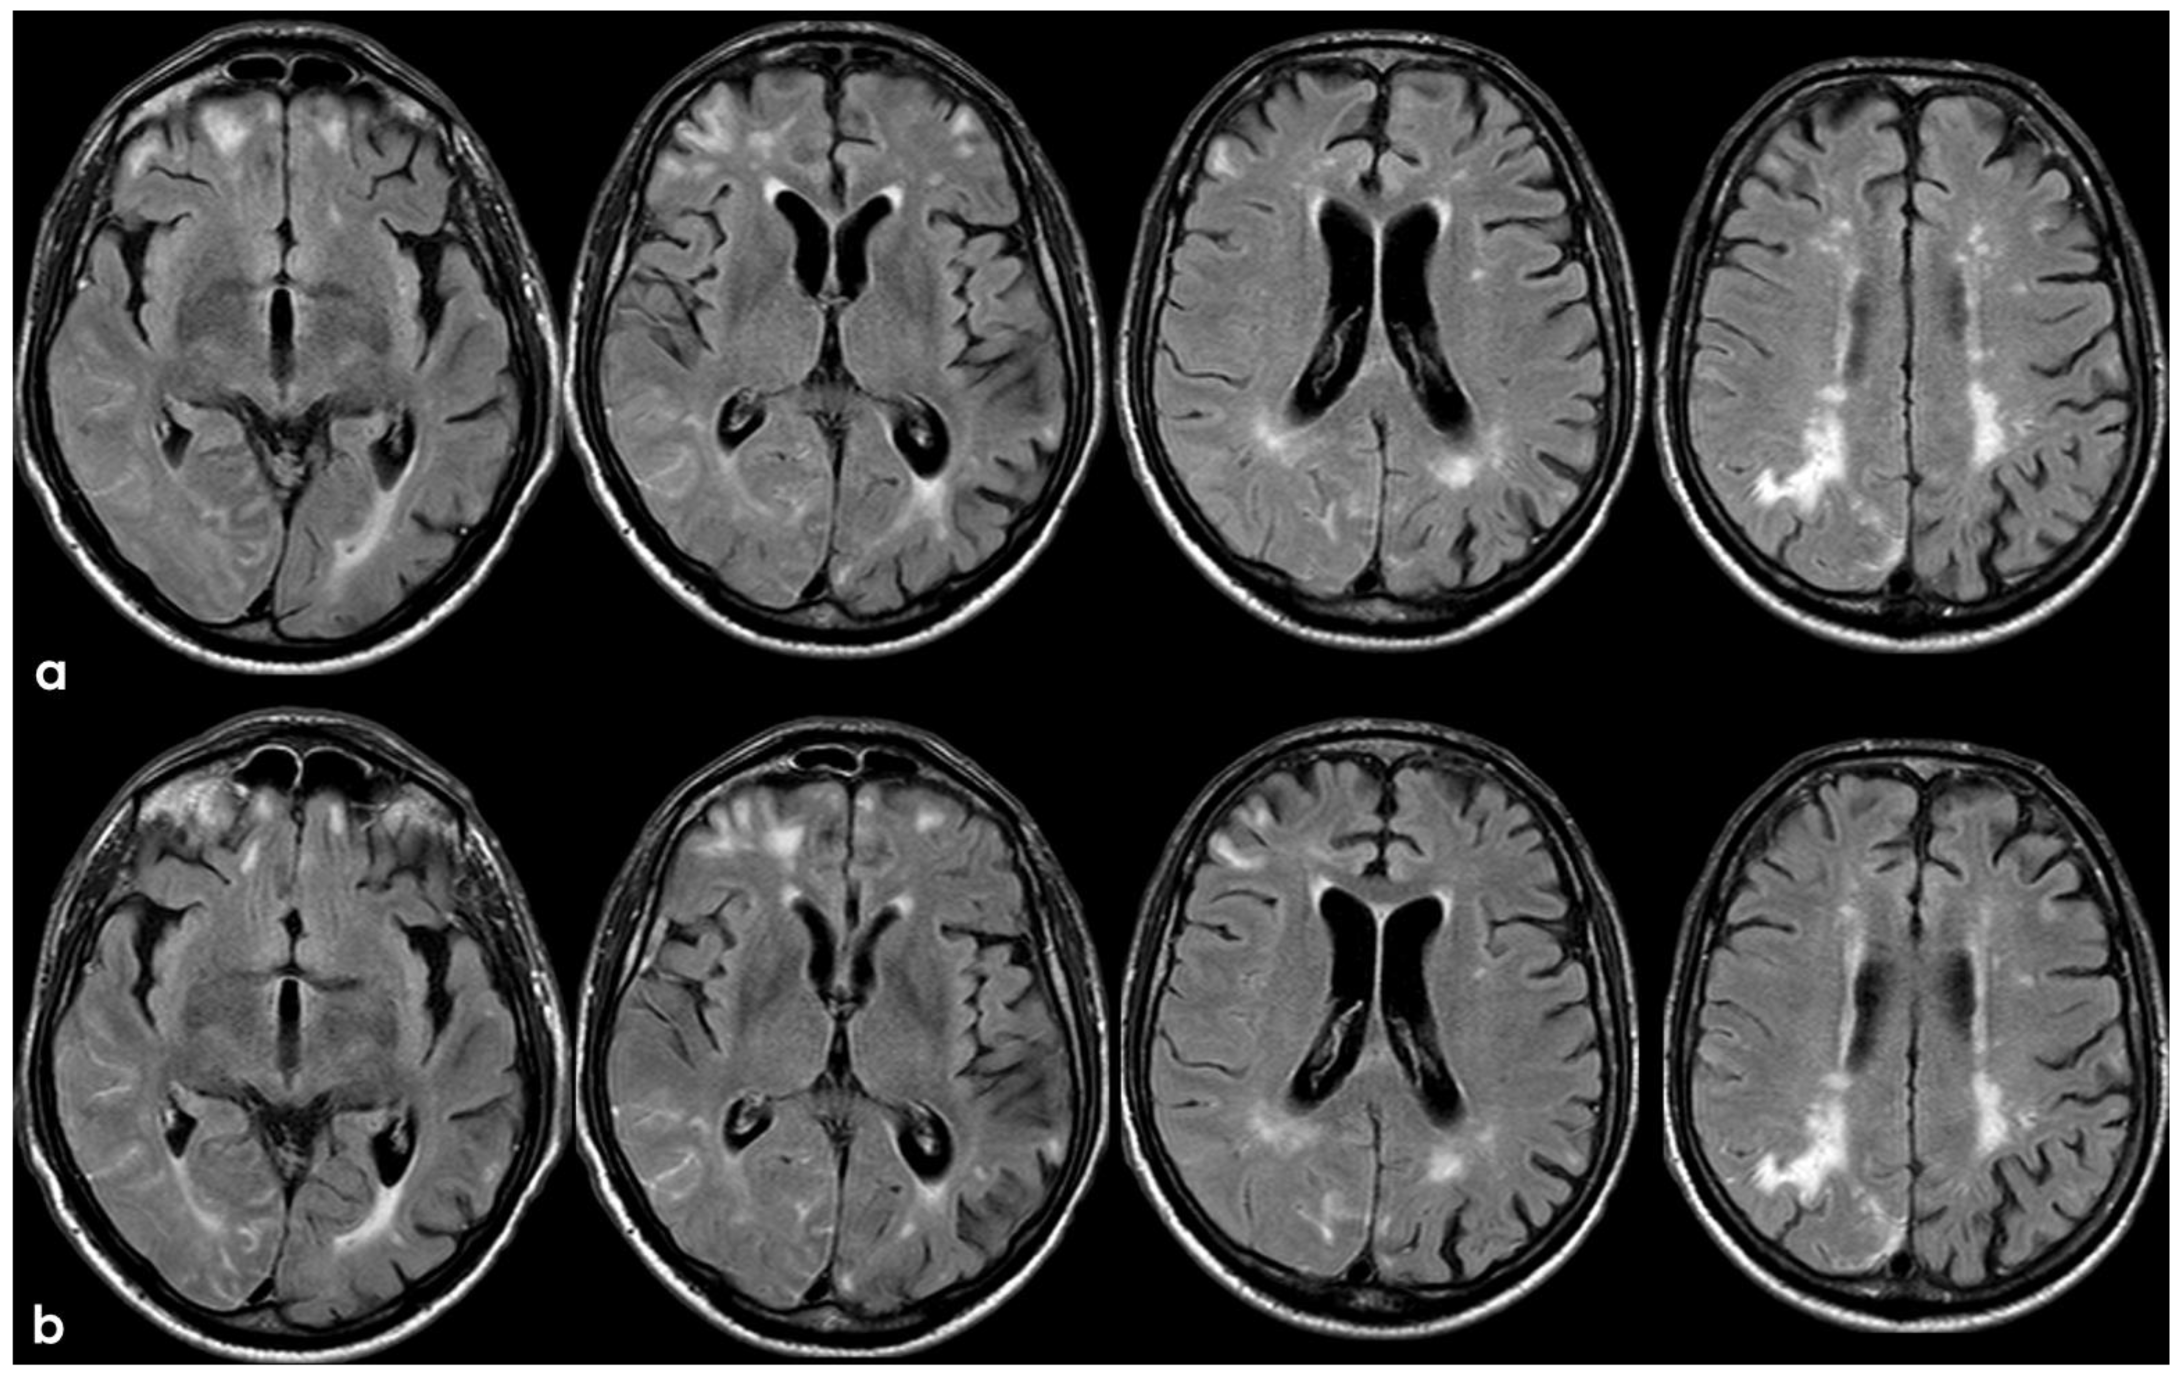

3. May 2014: CAA-Related Inflammation

5. February 2017: First Recurrent CAA-Related Inflammation

7. April 2018: Second Recurrent CAA-Related Inflammation

8. April 2018: Third Recurrent CAA-Related Inflammation